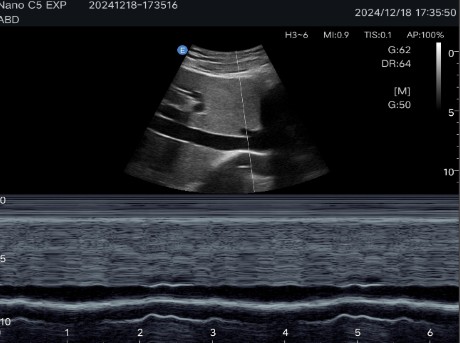

Abdominal diagnostics, obstetrics and gynecology: Allows detailed evaluation of internal organs and structures.

Multiple imaging modes: Includes B-mode, C-mode, M-mode and Pulsed Doppler (PW), ensuring precise visualizations for various clinical applications.